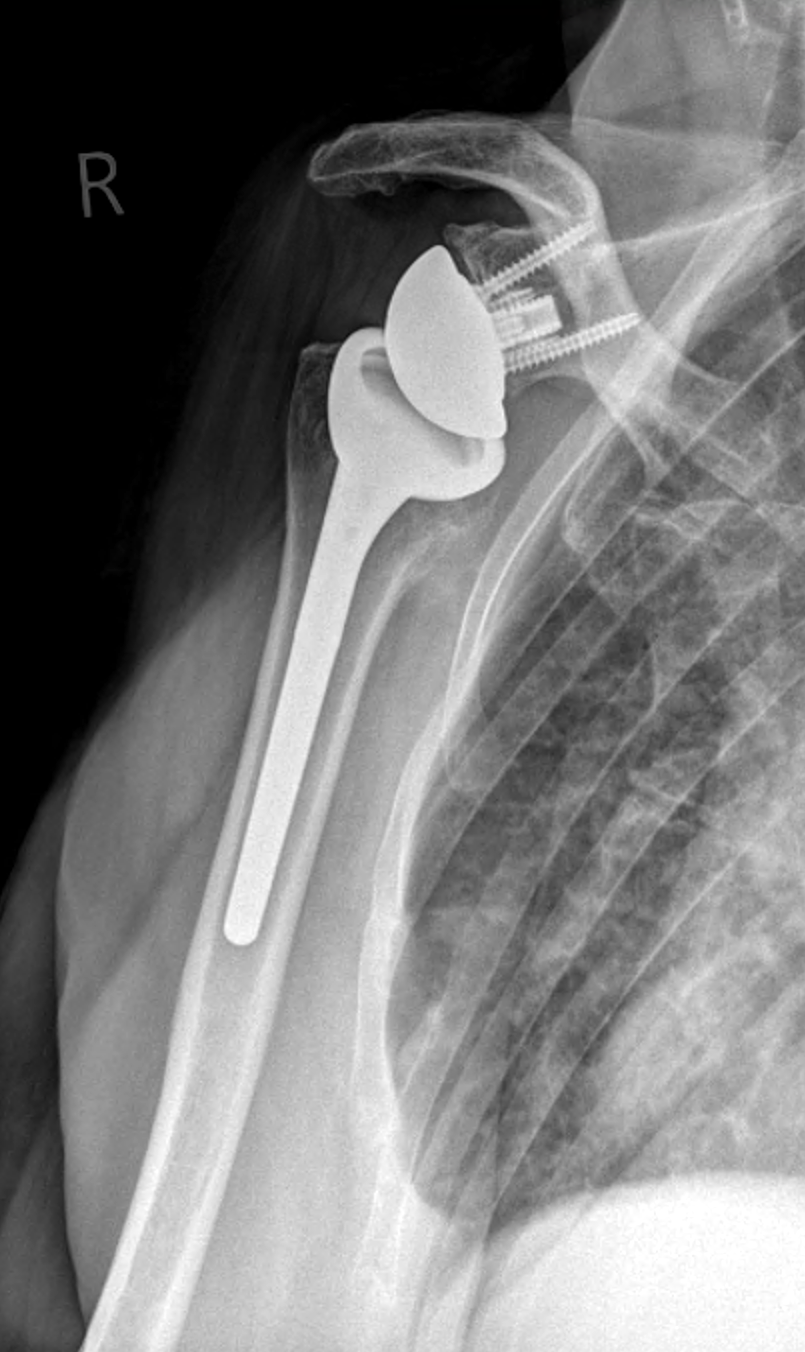

NEU im ZFOS: Schulterspezialist PD Dr. med. Bastian Scheiderer verstärkt Ärzteteam

Ab dem 1. Dezember 2025 begrüßen wir Privatdozent Dr. med. Bastian Scheiderer als zukünftigen Partner im ZFOS. Dr. Scheiderer ist...

ZFOS Prehab – Rehabilitation beginnt schon vor der Operation

Steht bei einem Patienten eine Prothesenoperation an Hüfte, Knie oder Schulter bevor, rückt das Thema Rehabilitation meist erst nach dem...